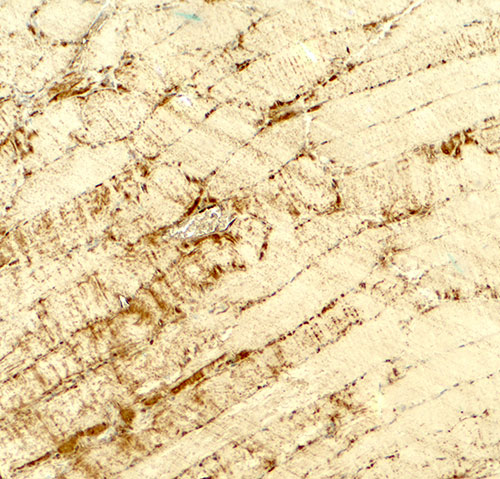

Immunohistochemistry of DCNP1 in mouse skeletal muscle tissue with DCNP1 antibody at 5 μg/ml.